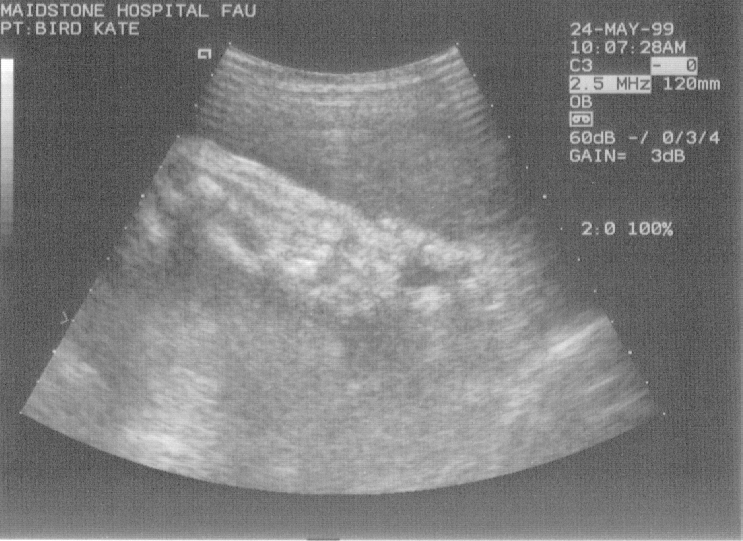

These are the six scans taken at the week–20 “abnormality scan”. Click on the thumbnail to view the full picture :-

Week 20, scan 1  (bust, side–on)